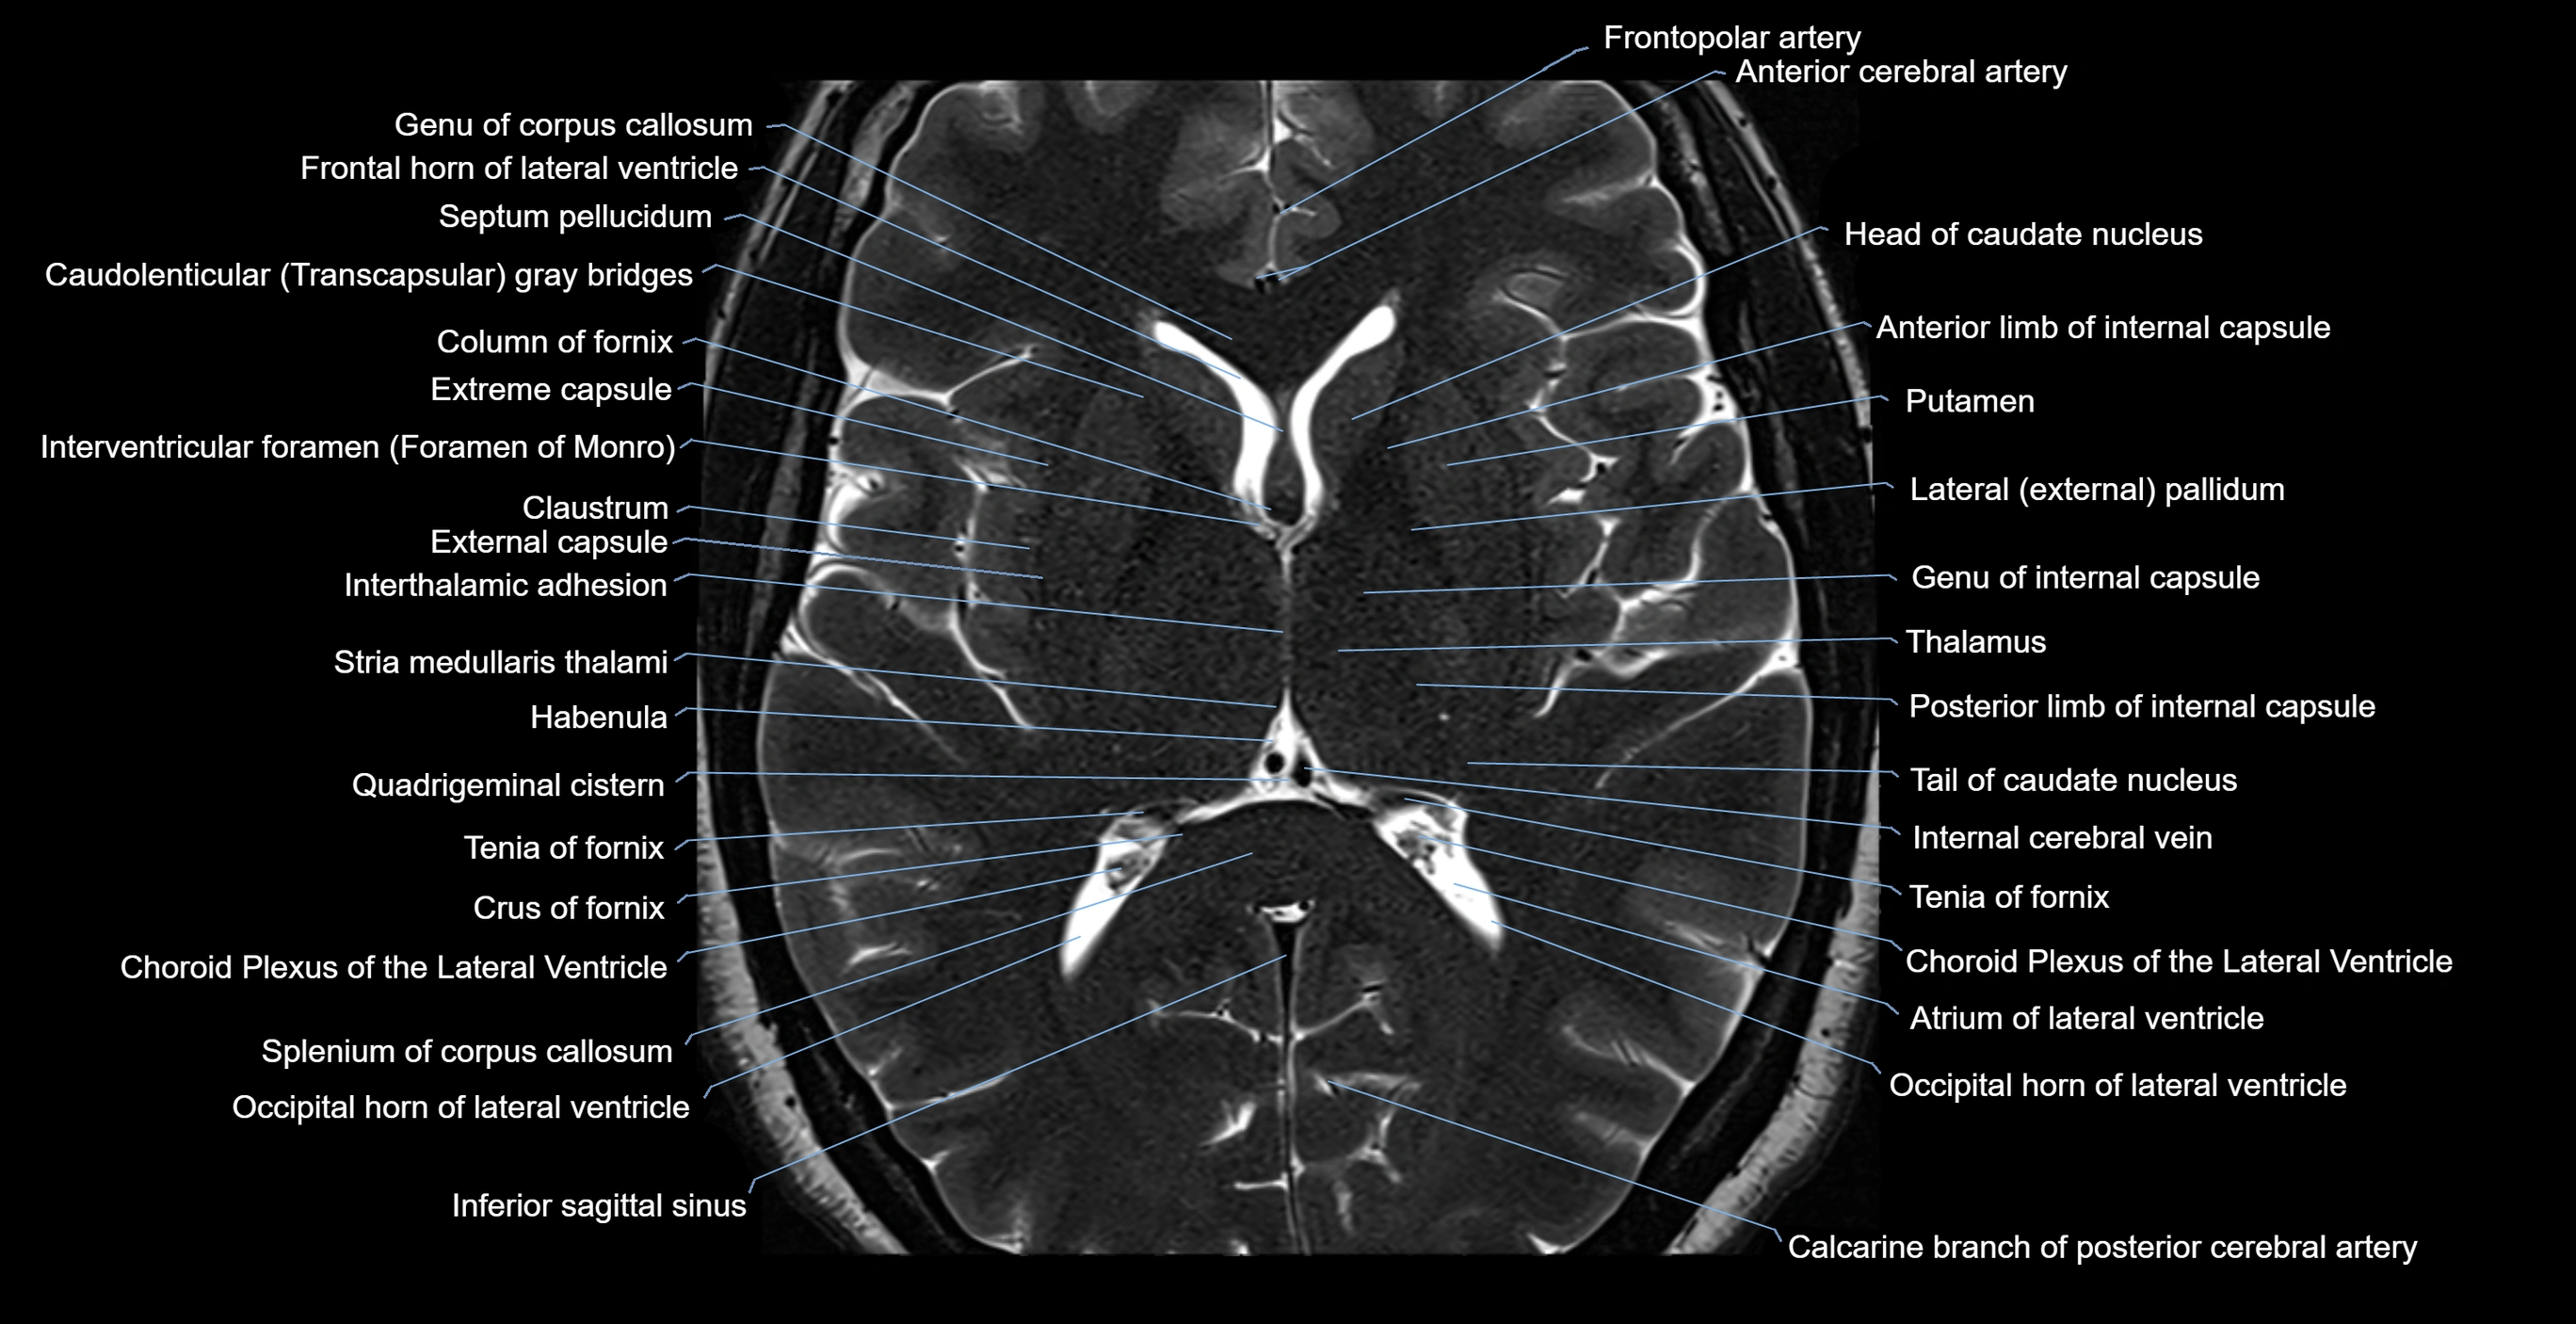

- Atrium of lateral ventricle

- Calcarine branch of posterior cerebral artery

- Caudatolenticular gray bridges

- Choroid plexus of the lateral ventricle

- Column of fornix

- Crus of fornix

- Frontal horn of lateral ventricle

- Frontopolar artery

- Genu of corpus callosum

- Habenula

- Inferior sagittal sinus

- Internal cerebral vein

- Interthalamic adhesion

- Interventricular foramen

- Occipital horn of lateral ventricle

- Septum pellucidum

- Splenium of corpus callosum

- Stria medullaris thalami

- Tail of caudate nucleus

- Tenia of fornix

- Thalamus

- genu of internal capsule